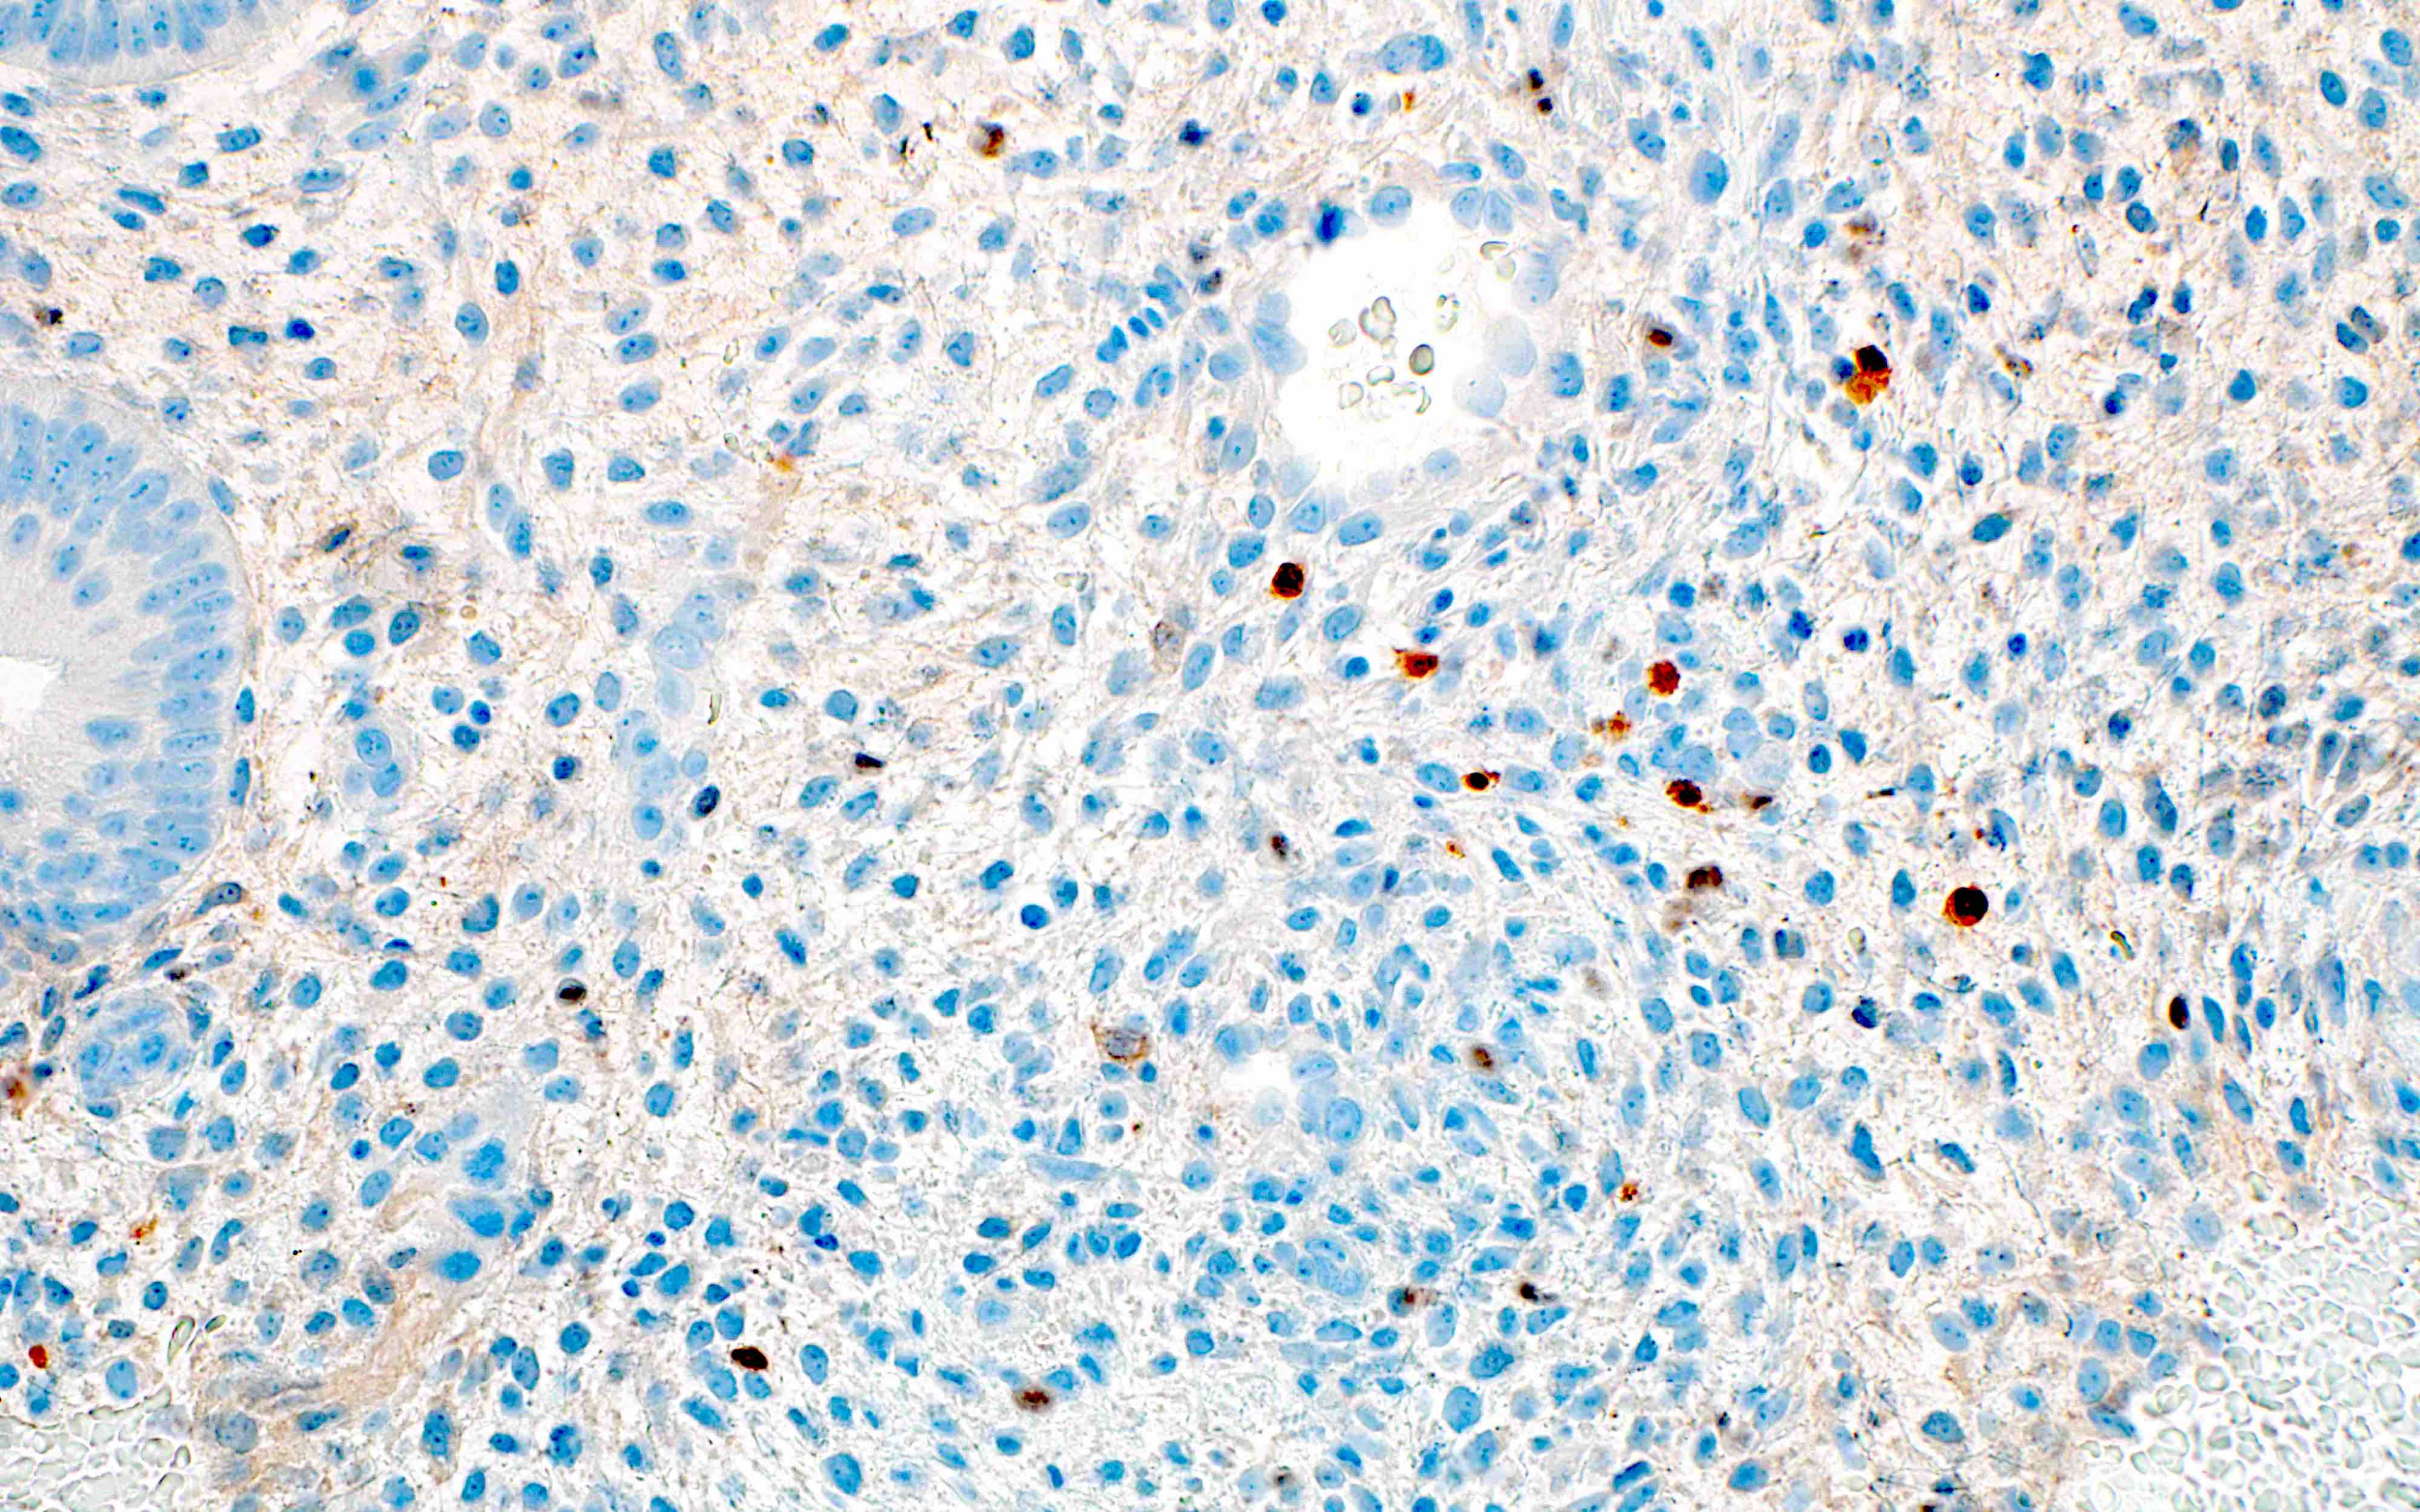

Microscopic (histologic) images

Contributed by Stephanie L. Skala, M.D. and Yuri Tachibana, M.D.

Chronic endometritis

Positive stains

- Chronic endometritis

- CD138 / syndecan in plasma cells (Arch Pathol Lab Med 2004;128:1000)

- MUM1 in plasma cells; higher sensitivity, cleaner background (Int J Surg Pathol 2019;27:372)